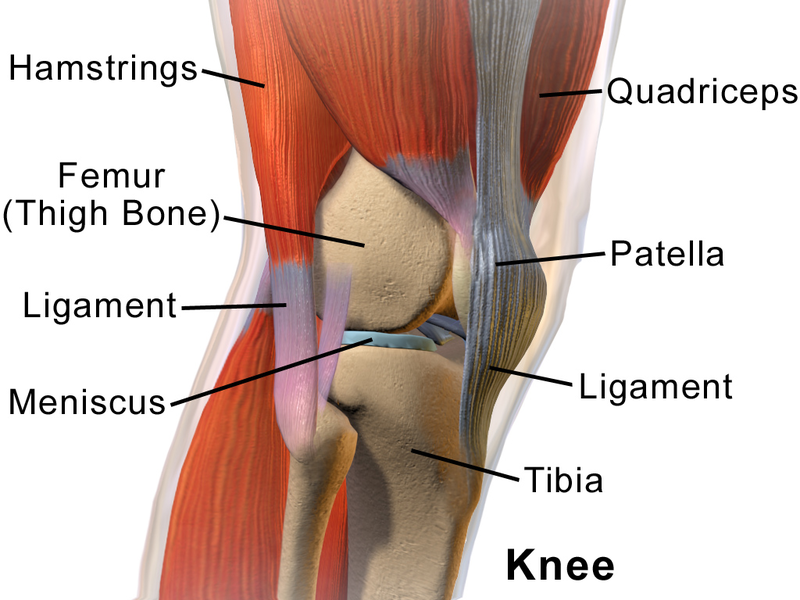

Knees are one of the most utilized joints of the human body. Because of this overuse, they are highly prone to damage. Several things can cause knee pain. Knee pain affects the quality of life as it creates an inability to bend or move around.

Knees are vital for our daily lives as they bear much of our body’s weight. There are several factors that can cause knee pain, ankle fracture , shoulder dislocation ranging from injuries and traumas to medical conditions. However, the following are the few ailments that can be linked to knee pain.

Kneecap dislocation is another common cause of knee pain that occurs when the kneecap does not properly align with the groove known as the trochlea. This groove is what the kneecap slides up and down on as the leg bends.

The iliotibial band is a thick band of fibrous tissue which goes down the outside of the leg, starting at the hip and ending at the outside of the shin bone. This band works with the quadriceps muscle and other thigh muscles in order to ensure that there is stability for the knee.